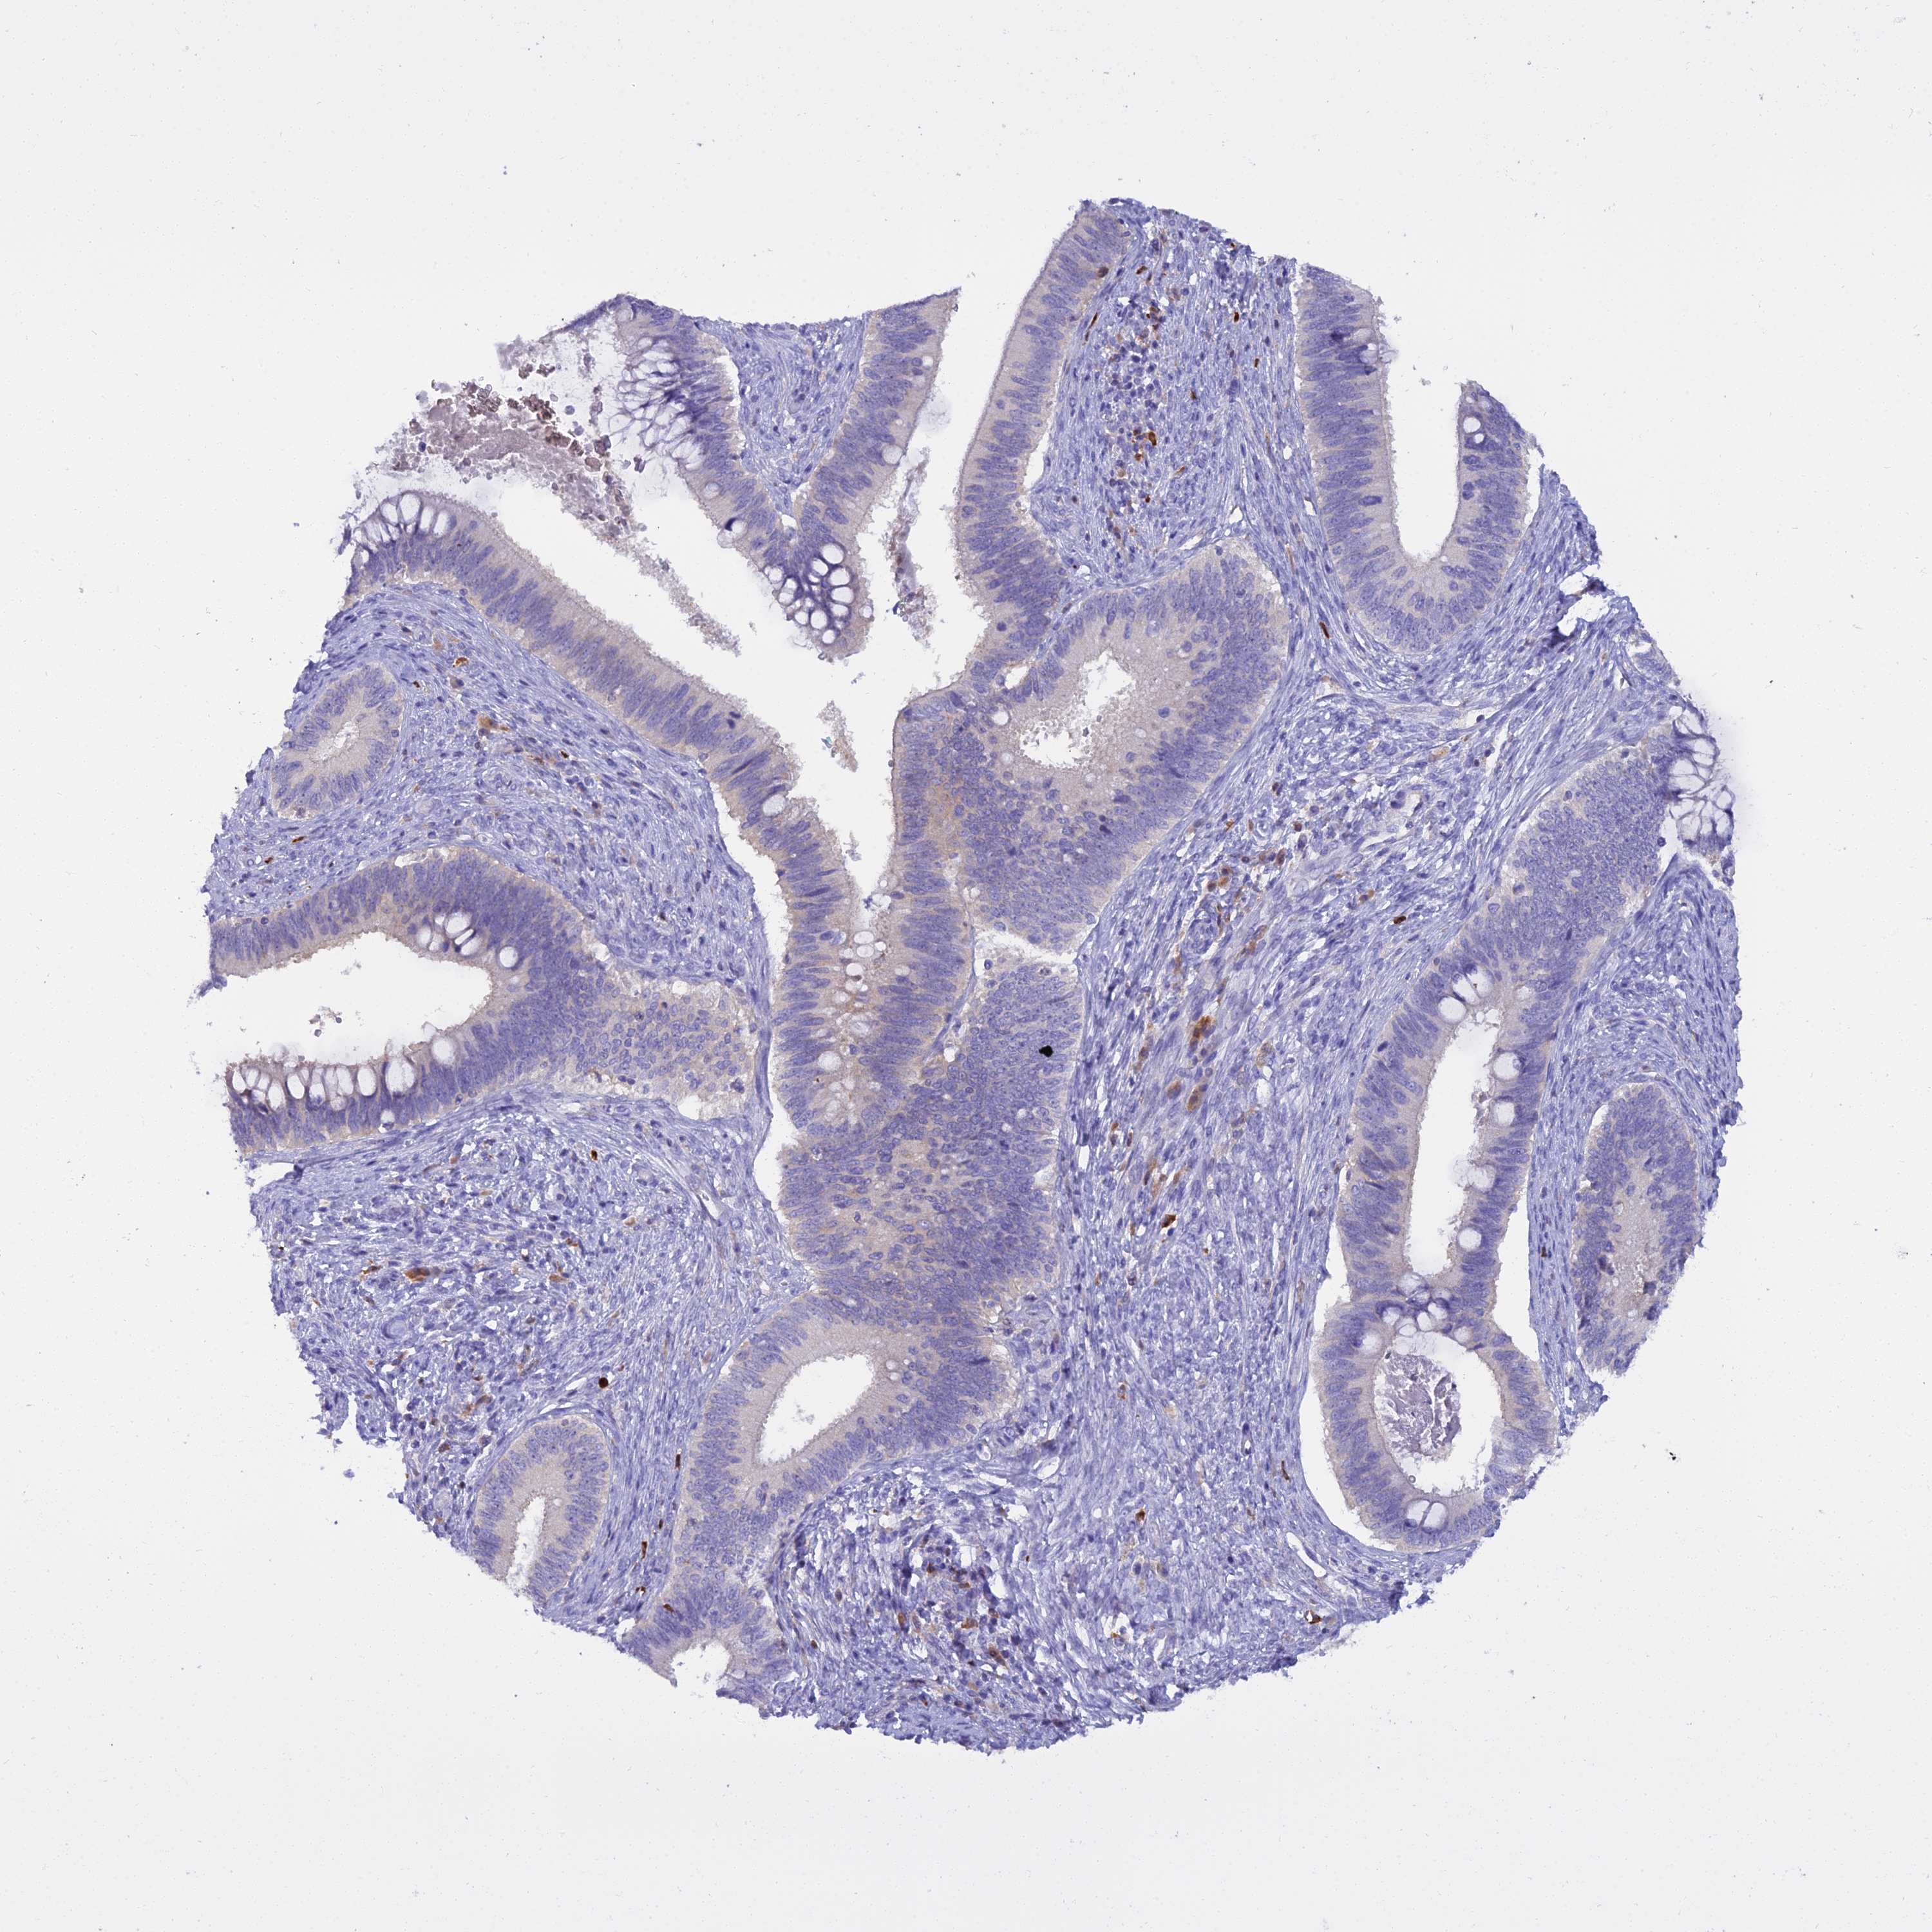

CERVICAL CANCER - Protein expressioni

A mouse-over function shows sample information and annotation data. Click on an image to view it in a full screen mode. Samples can be filtered based on level of antibody staining by selecting one or several of the following categories: high, medium, low and not detected. The assay and annotation is described here.

Note that samples used for immunohistochemistry by the Human Protein Atlas do not correspond to samples in the TCGA dataset.

Antibody stainingi

Antibody staining in the annotated cell types in the current human tissue is reported as not detected, low, medium, or high, based on conventional immunohistochemistry profiling in selected tissues. This score is based on the combination of the staining intensity and fraction of stained cells.

Each image is clickable and will lead to virtual microscopy that enables deeper exploration of all samples and also displays staining intensity scores, fraction scores and subcellular localization as well as patient and tissue information for each sample.

Antibody HPA038309

Antibody HPA038310

Antibody CAB009333

Antibody CAB016291

Adenocarcinoma, NOS